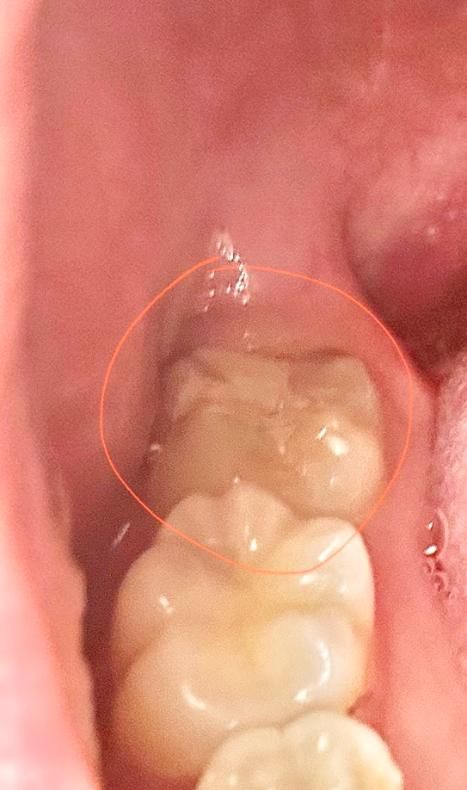

어금니 GI로 충치치료 받고 마취풀리니까 치통이 너무 심해요

오늘 치료 받았습니다 진통제를 섭취해야하나요? 진짜 너무 아파서 미쳐버릴거 같아요

충치가 깊으면 깊을수록 아프다고 들었는데 너무 아파요..

• 1번 째 사진